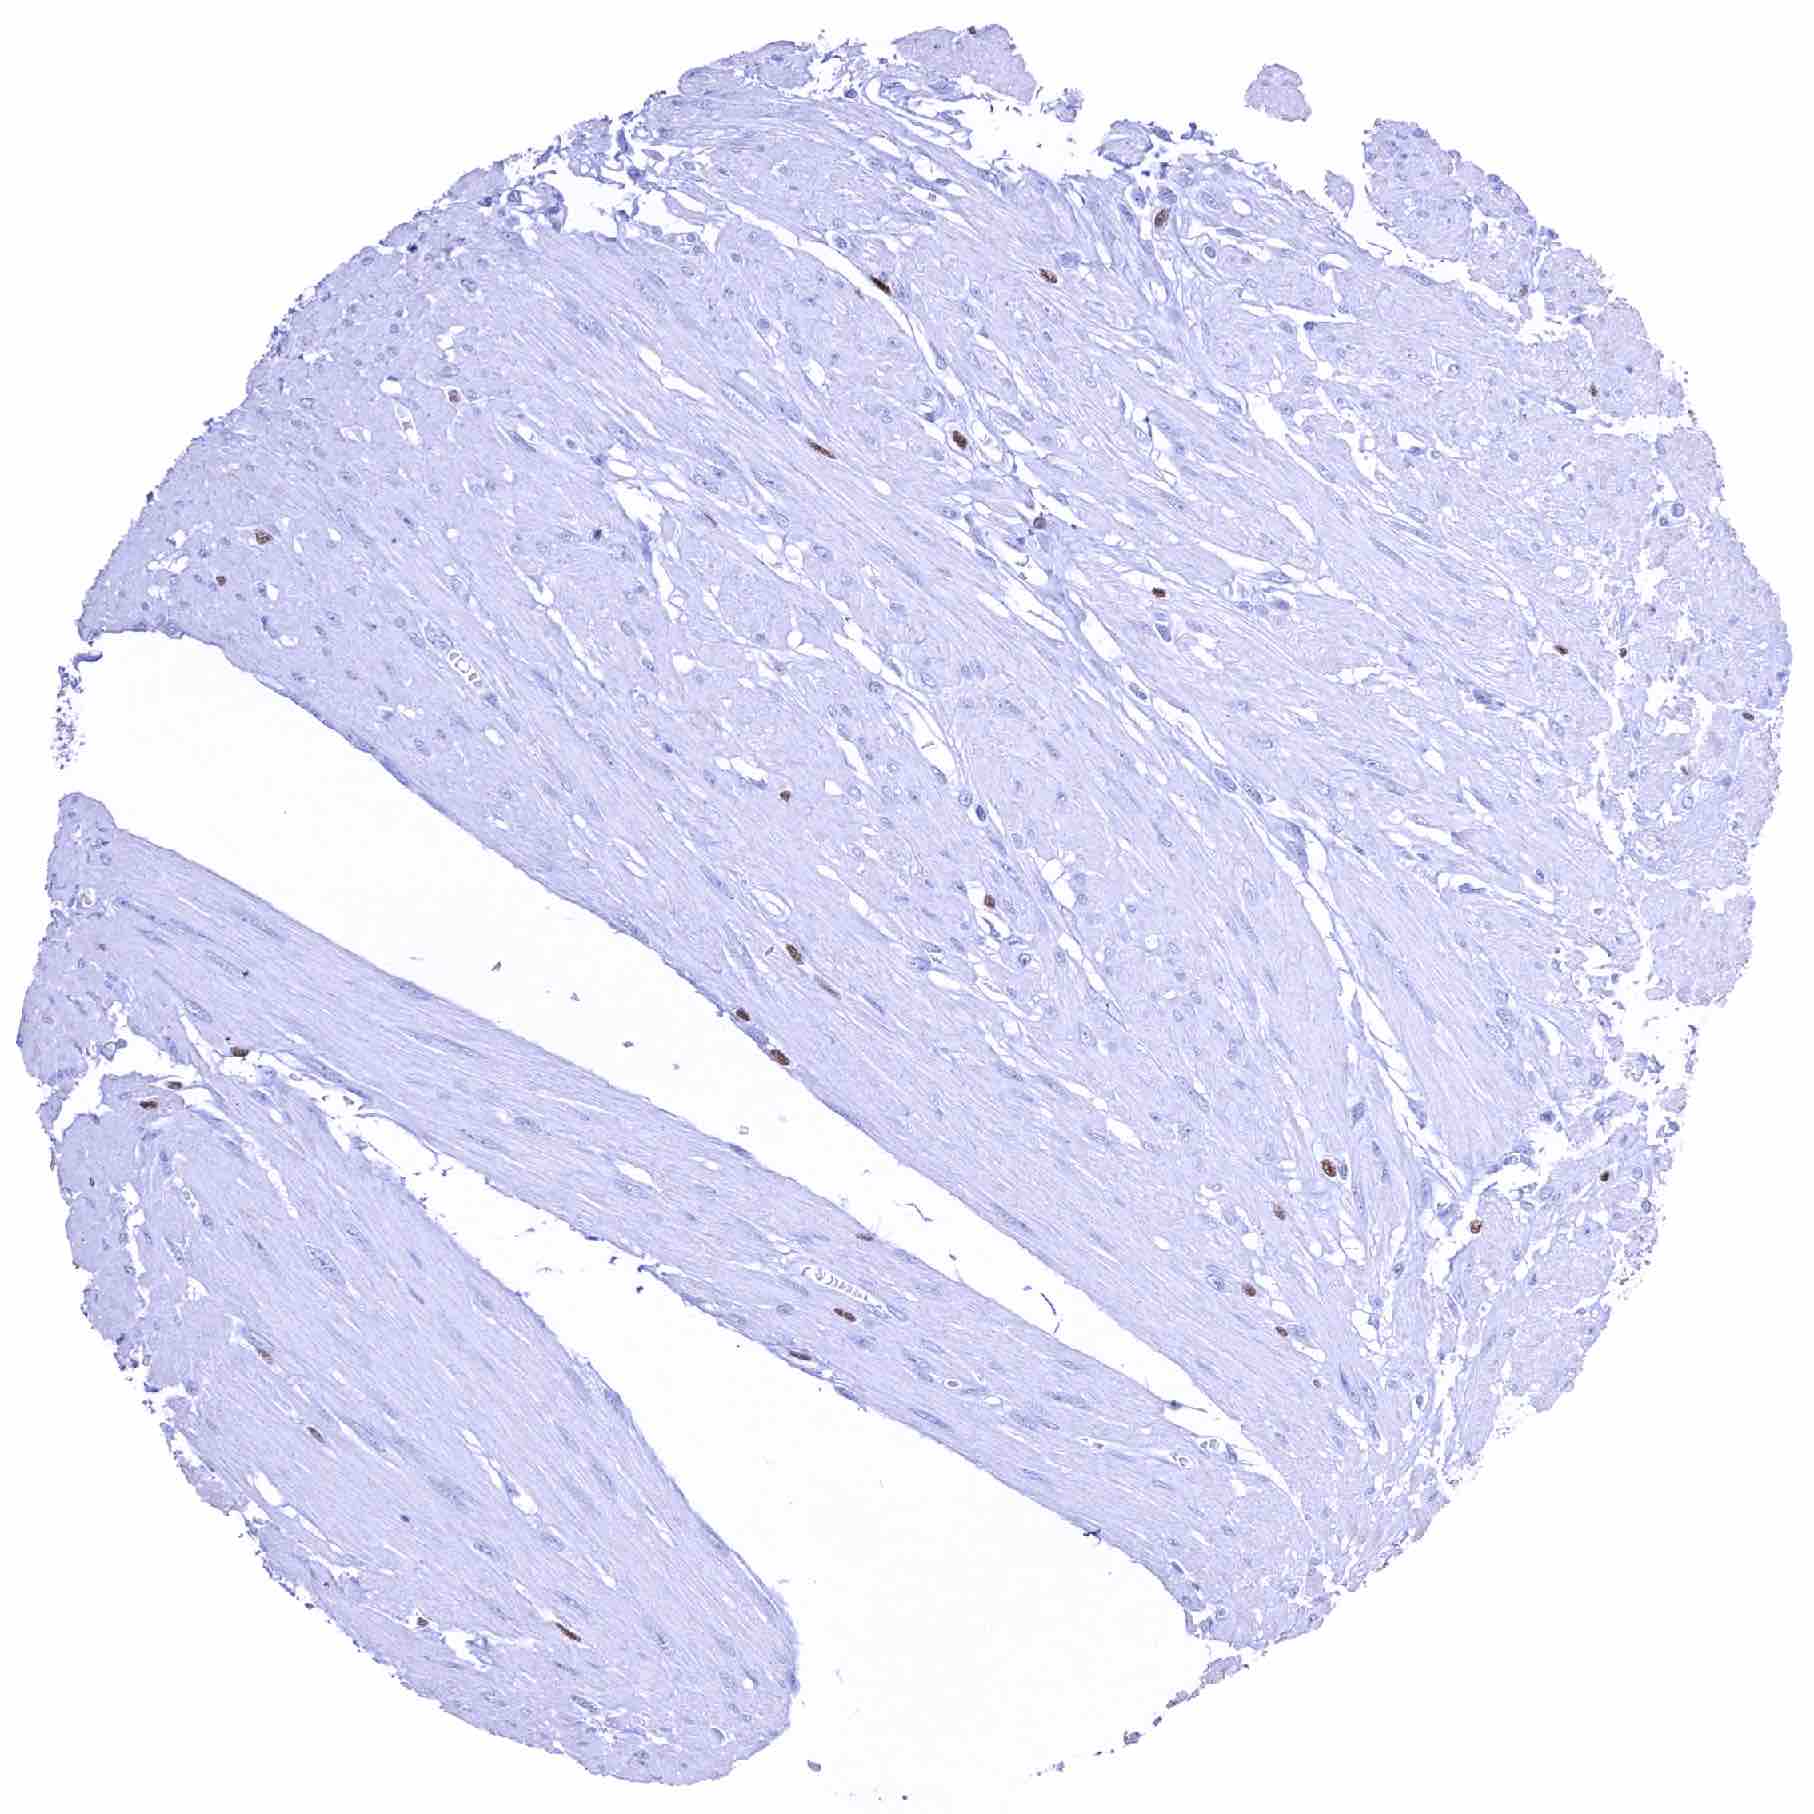

Uterus, myometrium